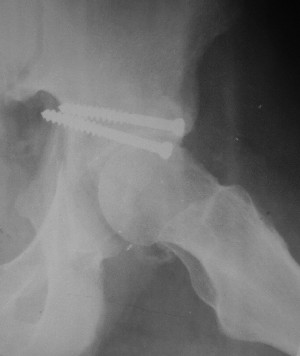

Привет! Вот недавно прооперировали похожий на ваш случай - впадина + шейка (правда у нас впадина поперечный+задний край). После травмы прошло 4 недели. мужчине 46 лет. С такой комбинацией все показания к первичному протезированию. Морально и технически мы к этому уже созрели.Но больной не собрал денег на протез. Выполнили остеосинтез впадины и шейки, прекрасно понимая, что головка вскоре рассосется, мы хотя бы надемся что к этому времени таз срастется, как говорится создали все условия для дальнейшего протезирования (может, и протез в последующем подешевле будет, в смысле, без укрепляющего кольца?). Привет Рункову!

Привет Алекей! Сделано неплохо, поздравляю, хотя второй винтик можно было бы и подлиннее в шейку загнать! Пара вопроов: доступ такой же? головка была свободной или висела на капсуле?

Согласен, можно было и подлиннее. Доступ такой же - чрезвертельный, только разрез кожи прямой (а не Y, чего то я разницы не ощущаю). Головка была абсолютно свободной (то есть во время остеосинтеза таза лежала в стакане и не мешалась). Шансов, что она прирастет 0,00001%. Хотели даже выбросить, но привинтили как временный биологический протез (читай свободный трансплантат), чтоб на период срастания таза бедро проксимально не ушло (может ортопеды потом спасибо скажут). Ну а у вас первичное протезирование при переломе впадины тоже пока полько в планах?